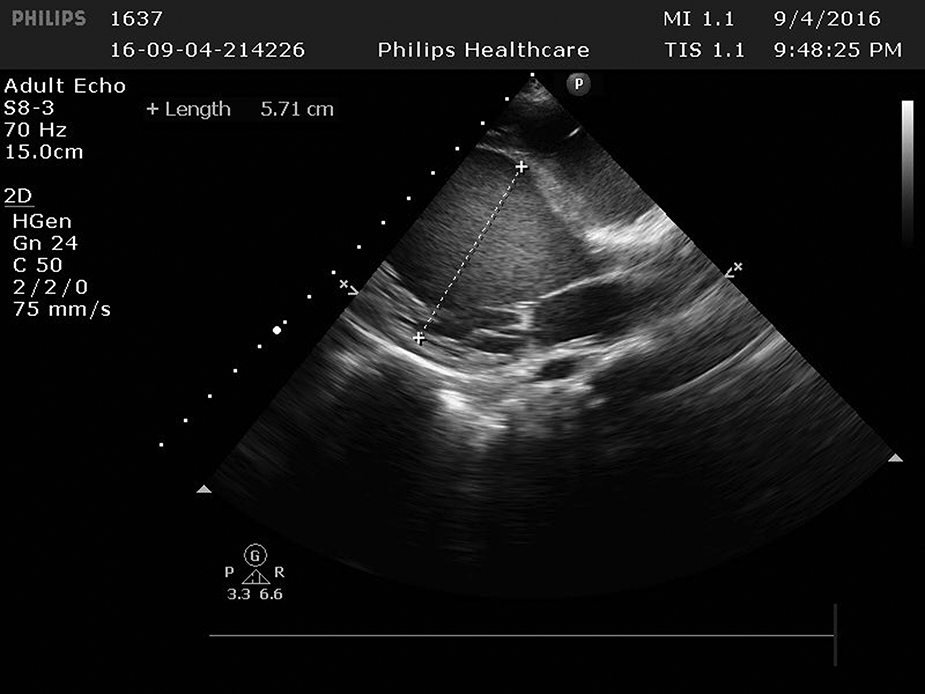

Figure 3

The left ventricle was significantly enlarged 5.71 cm.

Cardiac ultrasound: (1). interventricular septum thickness was fair. The motion amplitude of left ventricular wall was generally significantly reduced. Trabeculae were significantly increased and protruded into the ventricular cavity at the apex, lateral wall and inferoposterior wall of left ventricle, and deep lacunae were observed. The thickness of non-compacted myocardium was 10.5 mm and the thickness of compacted myocardium was about 3.9 mm. The ratio of the two was >2. CDFI showed that the blood flow signal communicating with the cardiac chamber in the recess. Fluid dark areas were observed in the pericardial cavity, measuring 7 mm in the dark area of the posterior wall of the left ventricle, about 10 mm in the dark area at the top of the right atrium, and about 8 mm in the dark area of the lateral wall of the right ventricle. Cardiac ejection fraction was 28%.